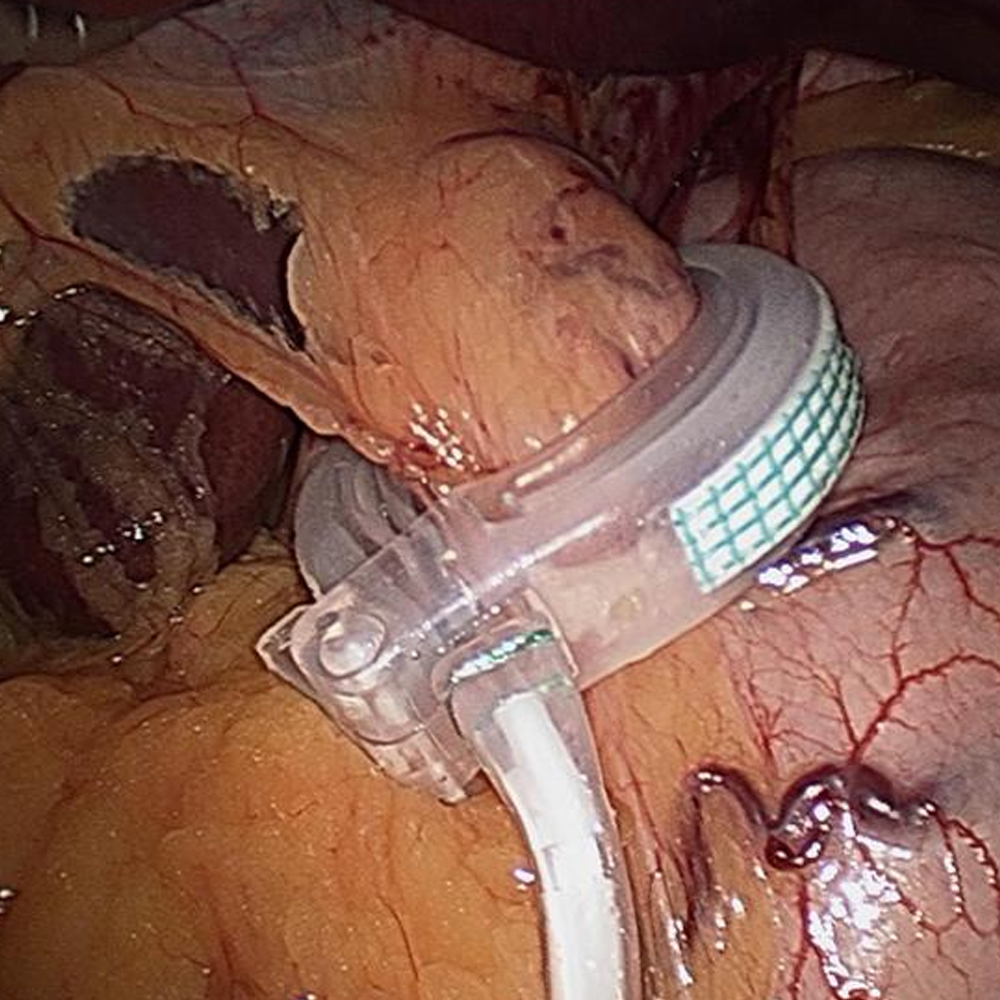

Laparoscopic gastric plication has emerged as a new bariatric procedure with promising results. This paved the path for further innovation and conception of a new procedure known as “Laparoscopic Adjustable Gastric Banded Plication”. This dual restrictive procedure involves gastric greater curvature placation or infolding of the stomach to form a gastric sleeve followed by placement of an adjustable band in the upper part of the stomach.

Laparoscopic adjustable gastric banded plication (LAGBP)

Combination of Gastric plication and gastric banding makes it dual restrictive with powerful weight loss comparable to sleeve gastrectomy and gastric bypass surgery. The rationale behind this surgery is that the plication “switches on” the initial weight loss process. Then adjustment of band further initiates the second phase of weight loss and maintains the success through serial adjustments. In addition to quicker weight loss from gastric plication, far less adjustments are required than with just having the band alone. In LAGBP, the disadvantages of gastric banding and gastric plication are taken off by each other. Gastric band doesn’t let plication to dilate over a period of time and gastric band doesn’t slip now because of the plicated stomach.

Unlike other bariatric surgery procedures, there is no stapling involved with LAGBP. No part of the stomach or intestines is cut or removed either. They are just folded from within followed by band placement. LAGBP can be reversed to normal anatomy or revised to any other procedure.